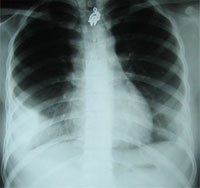

一例:患者女、18岁,两个月前反复活动后气短、胸闷、胸痛,自以为是高考压力大而致,未检查。疼痛、气短加重后检查为包裹性胸膜炎。如图:

右侧结核性胸膜炎胸膜包裹